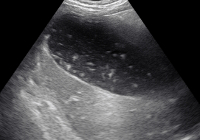

Для подтверждения диагноза в первую очередь осуществляют УЗИ желчного пузыря. Эхогенная картина не слишком специфична и достаточно изменчива. На мониторе можно увидеть изменение структуры, толщины стенок, значительное увеличение объема пузыря. Внутри органа визуализируется скопление желчи, возможно с газовыми пузырьками, неоднородным осадком, хлопьями. В перипузырном пространстве обнаруживается выпот и скопление жидкости.